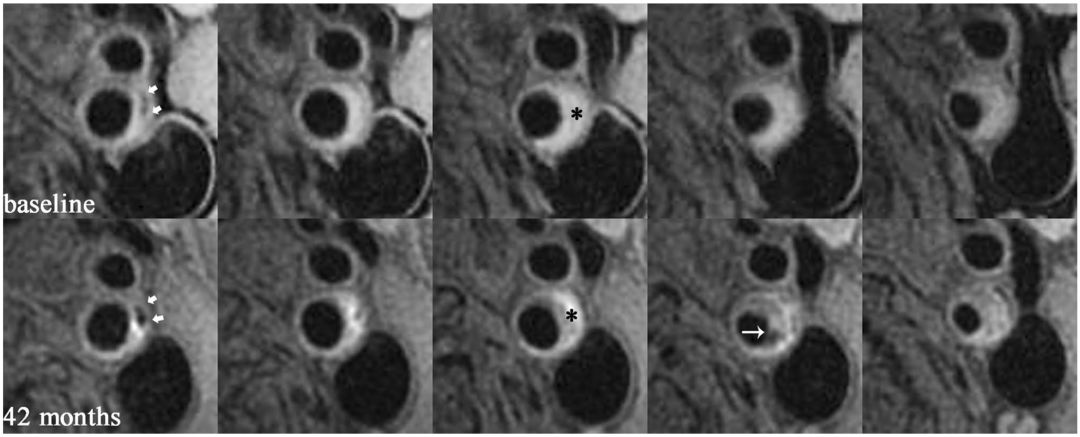

81岁男性患者,在T1W图像上左侧颈内动脉有钙化(短箭头)和斑块内出血(星号), 42个月后观察到新的纤维帽破裂(长箭头)